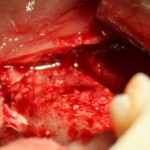

Например, в следующей ситуации:

Оставить так, как есть — это значит, сильно рисковать имплантом и объемом альвеолярного гребня — фактически, большая часть импланта пятого зуба «висит в воздухе». Поэтому получившуюся костную полость мы заполняем аутокостной стружкой в смеси с Bioss и закрываем коллагеновой мембраной BioGide: